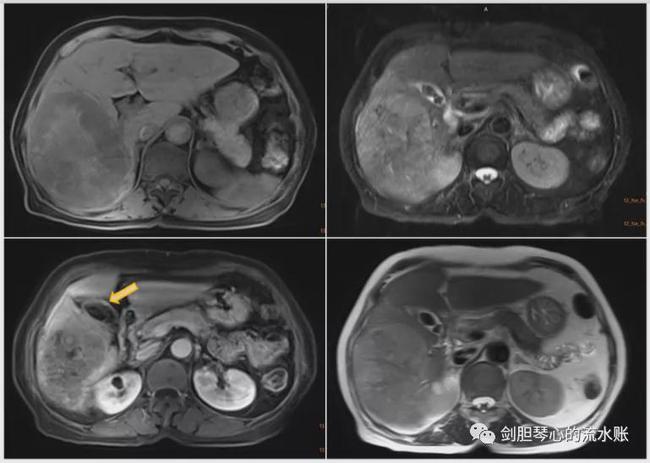

当时检查发现患者呈消瘦状态,腹部无明显阳性体征。血常规、肝肾功能正常,肿瘤标志物CEA、CA-199、CA-125正常,而肝癌的特异性指标AFP> 1210ng/mL,明显升高。腹部增强CT检查发现肝右叶有直径13cm大小的占位性病变,考虑肝癌;腹部MRI检查同时提示为肝右叶巨大肝癌、多发胆囊结石及胆囊壁局部增厚结节(如图1)。

考虑病人有肝硬化、年龄大、肿瘤巨大且推移下腔静脉明显,先做了经动脉栓塞化疗术(TACE),4周之后对侧肝增大、肿瘤的相对体积比变小以后,实施了标准的合并胆囊的右半边切除+肝门部淋巴结清扫术。术后病理证实,患者肝脏为中分化肝细胞癌,胆囊病变是具有内分泌倾向的低分化胆囊腺癌。术后顺利恢复出院。随诊2年未见复发及转移。